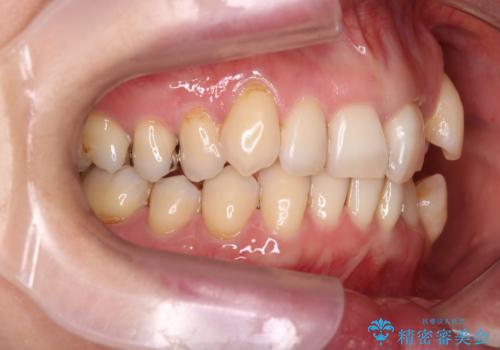

- 上下の歯の凸凹を主訴に来院されました。

他院では抜歯+ワイヤー矯正の提案をされているとのことでした。

当院での検査にて非抜歯+インビザライン矯正を提案させていただき治療を行なっております。

患者様にしっかりとインビザラインを使用して頂けたことで綺麗な仕上がりとなりました。